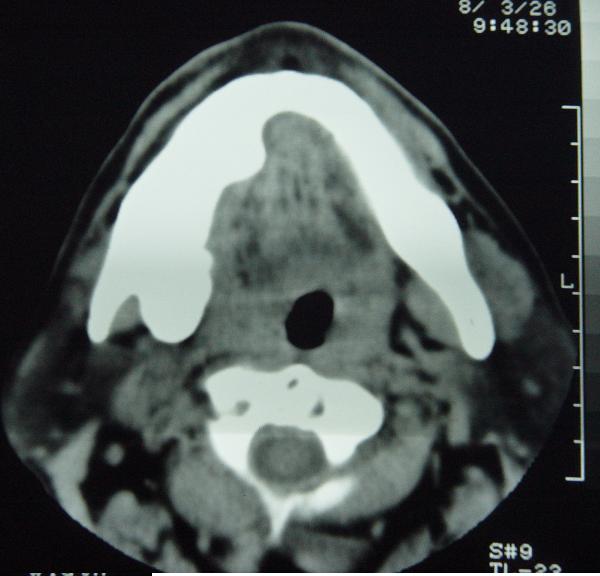

标题: CT12465:下颌骨肿瘤,请会诊 [打印本页]

标题: CT12465:下颌骨肿瘤,请会诊

发现下颌骨肿瘤近30年.逐渐增大.

考虑右侧下颌骨水平部及升部骨纤维异常增殖症可能性大。

造釉细胞瘤,没有特征性;半月切迹?骨间隔?多房性骨密度减低区,大小不等。鉴别;动脉瘤样骨囊肿,骨软骨瘤。本人,更倾向于---骨软骨瘤。

考虑右侧下颌骨骨化性纤维瘤。